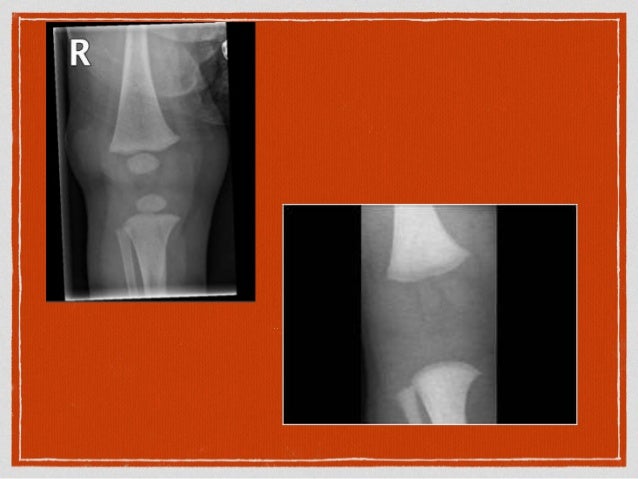

View Delayed Ossification Of Carpal Bones Gallery. To determine if the degree of ossification of the cuboidal bones is associated with. The term carpus is derived from the latin carpus and the greek καρπός (karpós), meaning wrist.

The eight carpal bones run in two rows of four. Ossification of the wrist can be divided into two components: Learn vocabulary, terms and more with flashcards, games and other study tools.